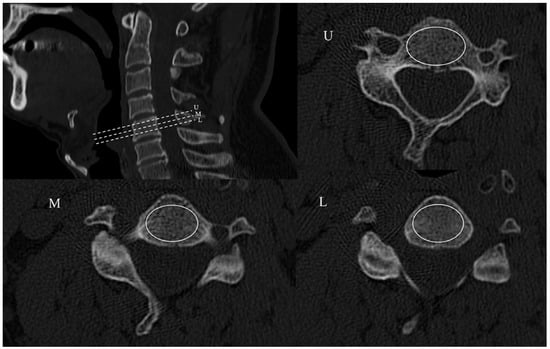

2.2. Radiographic Assessment